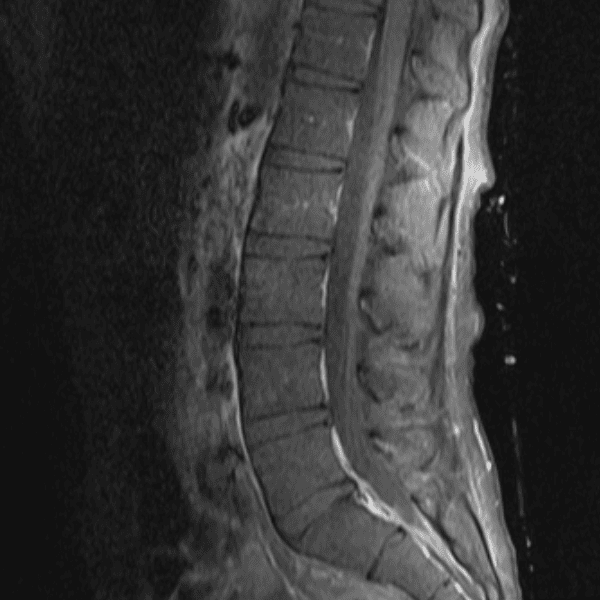

Simulates call by including subtle or difficult cases and some normals.

35 cases